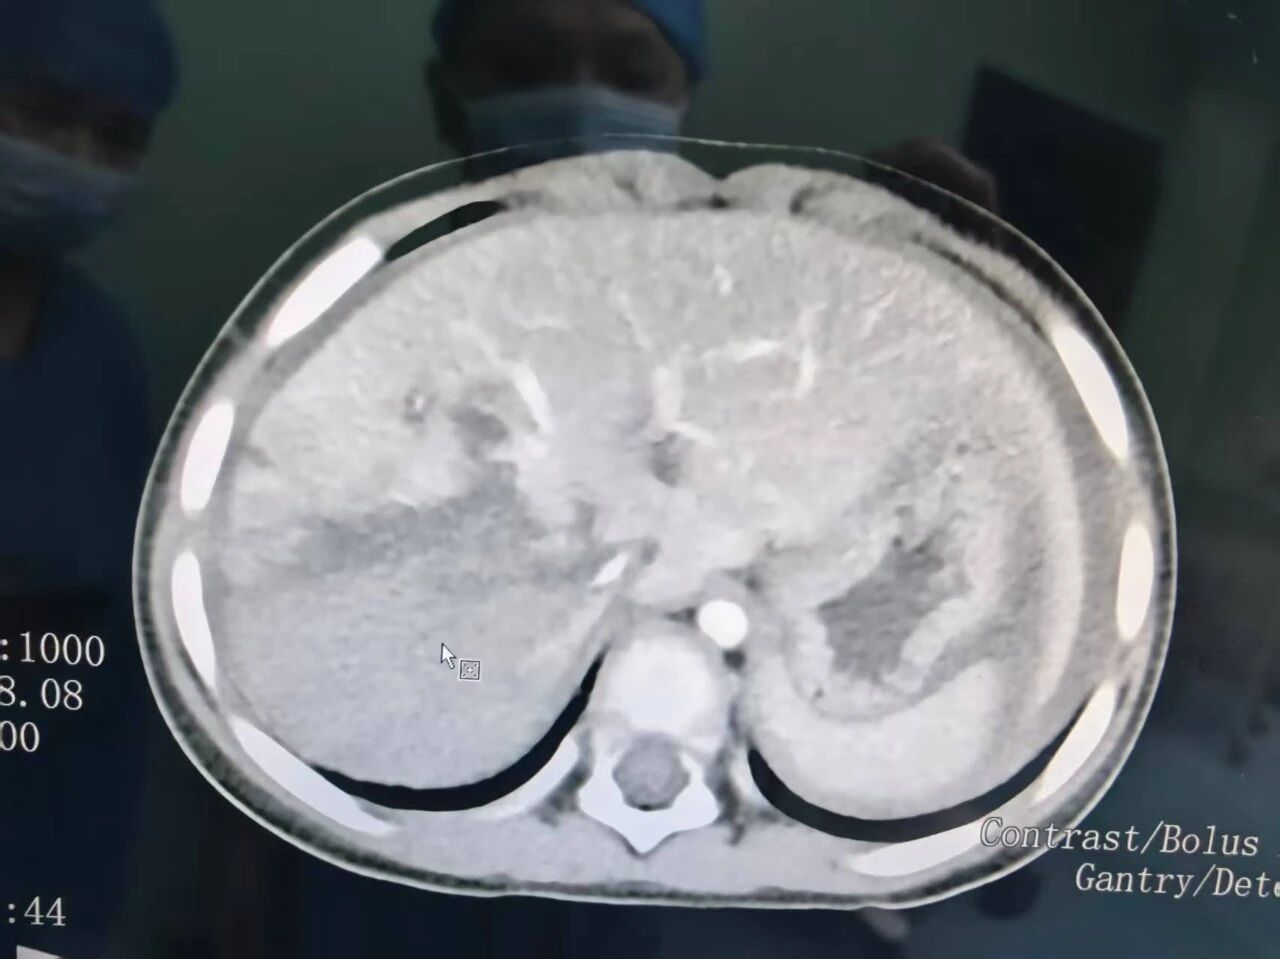

赶到手术室时,情形比他们预料的还要危急。患儿心率急剧下降,血压极度不稳,血色素低至 3 克,尿量全无,已经陷入休克状态。术前 CT 显示,患儿的肝脏右后叶完全毁损,血肿扩展,从第一肝门一直裂伤至第二肝门,无法修复。